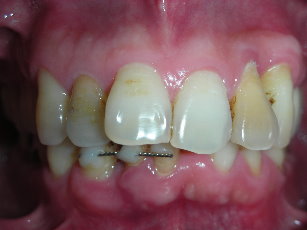

前牙修復及立即植牙-蛀牙-#13-23

人工植牙

立即植牙-前牙

前牙立即植牙-蛀牙-#13

局部拔牙術之立即植牙-牙齒斷裂-#22

立即植牙-下顎側門齒嚴重牙周病